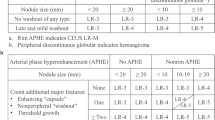

Attempts to improve standardization in the interpretation, documentation and reporting of contrast-enhanced imaging led to the development of LI-RADS (Liver Imaging Reporting and Data System) by the American College of Radiology (ACR) in 2011 [9, 10]. With LI-RADS, focal liver lesions in high-risk patients are categorized according to “major features” (lesion diameter, arterial phase hyperenhancement, washout appearance, capsule appearance, threshold growth) and optionally using ancillary features. The probability of a lesion being an HCC is expressed by assigning a LI-RADS category between LR-1 (definitely benign) and LR-5 (definitely HCC). LI-RADS is only defined for observations in contrast-enhanced computed tomography (CE-CT) and magnetic resonance imaging (CE-MRI).

CEUS-LI-RADS

CEUS examinations were evaluated according to ACR-CEUS-LI-RADSv.2016 (Supplemental Fig. 1) developed by the American College of Radiology. Prior to the study, observers received theoretical training (2 h) to become familiarized with the use of the CEUS-LI-RADS algorithm. The algorithm and its features were explained and example CEUS clips of all categories were reviewed. In a subsequent practical training phase, classification according to CEUS-LI-RADS was taught using five example lesions.

Two observers with 2 and 5 years of experience, respectively, in CEUS examinations of the liver blinded to patients’ clinical data and final diagnosis (except for knowledge of a high-risk constellation) independently reviewed the CEUS examinations and assigned a CEUS-LI-RADS category to the target observation. Observers assessed uptake of contrast agent in the target observation relative to the surrounding parenchyma. They decided on hyper-, iso- or hypoenhancement of the target observation in the arterial, portal venous and late phase and, if available, very late phase (> 240 s). In case of “washout”, observers were asked to distinguish between early “washout” (starting < 60 s) and late “washout” (≥ 60 s).

MRI-LI-RADS

MRI examinations were evaluated according to LI-RADSv.2014 (Supplemental Fig. 2). One certified radiologist with 7 years and one resident with 4 years of experience in hepatobiliary imaging blinded to patients’ clinical data and final diagnosis (except for knowledge of a high-risk constellation, location and size of the target observation) independently reviewed the MRI examinations and assigned a LI-RADS category to the target observation.

Ancillary features and tie-breaking rules were not used. As MRI scans were available for one examination per patient, the major feature of “threshold growth” could not be assessed.